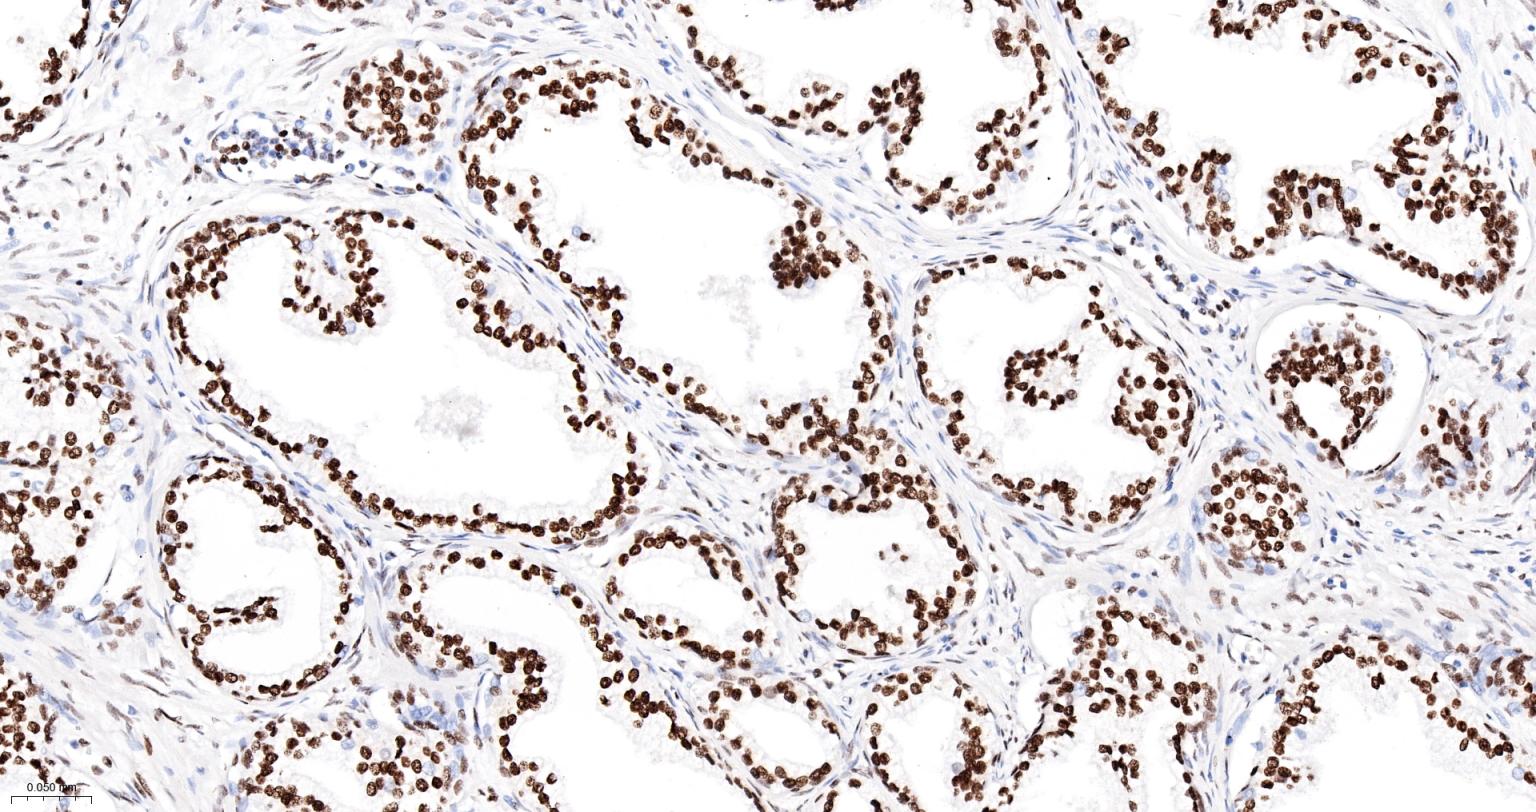

Paraformaldehyde-fixed, paraffin embedded Human Lung Cancer; Antigen retrieval by boiling in sodium citrate buffer (pH6.0) for 15 min; The section was incubated with ARID1A Monoclonal Antibody, Unconjugated (bsm-61359R) at 1:200 overnight at 4°C, followed by conjugation to the bs-0295G-HRP and DAB (C-0010) staining.